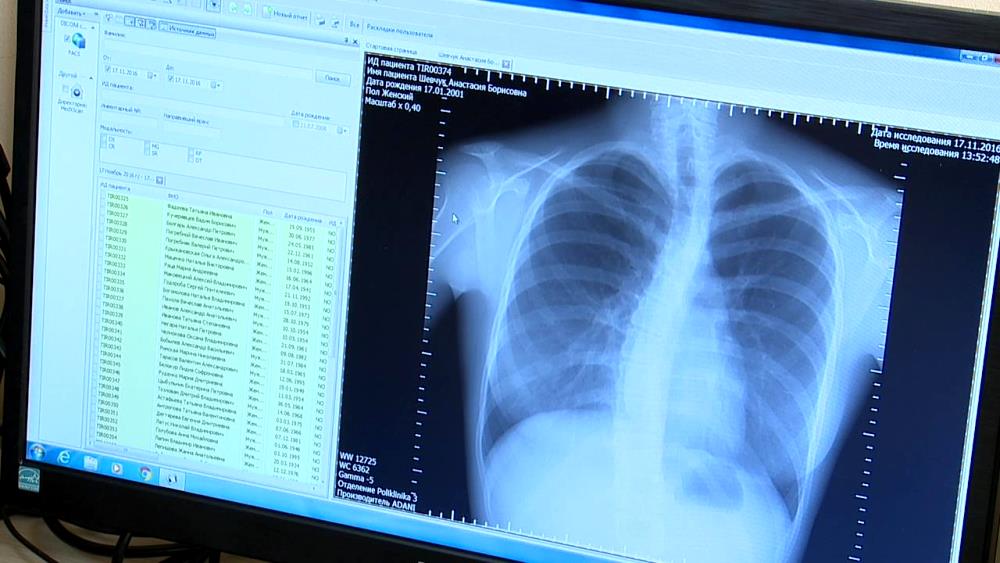

Тирасполь, 18 ноября. / ИА «Новости Приднестровья»/. В столичной поликлинике №3 начал работу современный флюорографический аппарат. Работающий на цифре он превосходит своего аналогового предшественника по всем параметрам – и по скорости, и по качеству картинки. Первое достигается за счёт практически моментального получения снимка – без необходимости проявления плёнки и использования химреактивов. Он заносится в электронную базу, историю болезни пациента и, в случае необходимости, может пересылаться другому врачу. Качество – тоже несравнимо со старым.

«Можно сразу увидеть снимок, выделить нужную область, сделать снимок более или менее контрастным. Это, конечно, гораздо более удобно по сравнению с плёночными мелкокадровыми снимками. Там был задействован процесс химической обработки, могли появляться дефекты», – рассказала заведующая рентгенотделением Светлана Звягина.